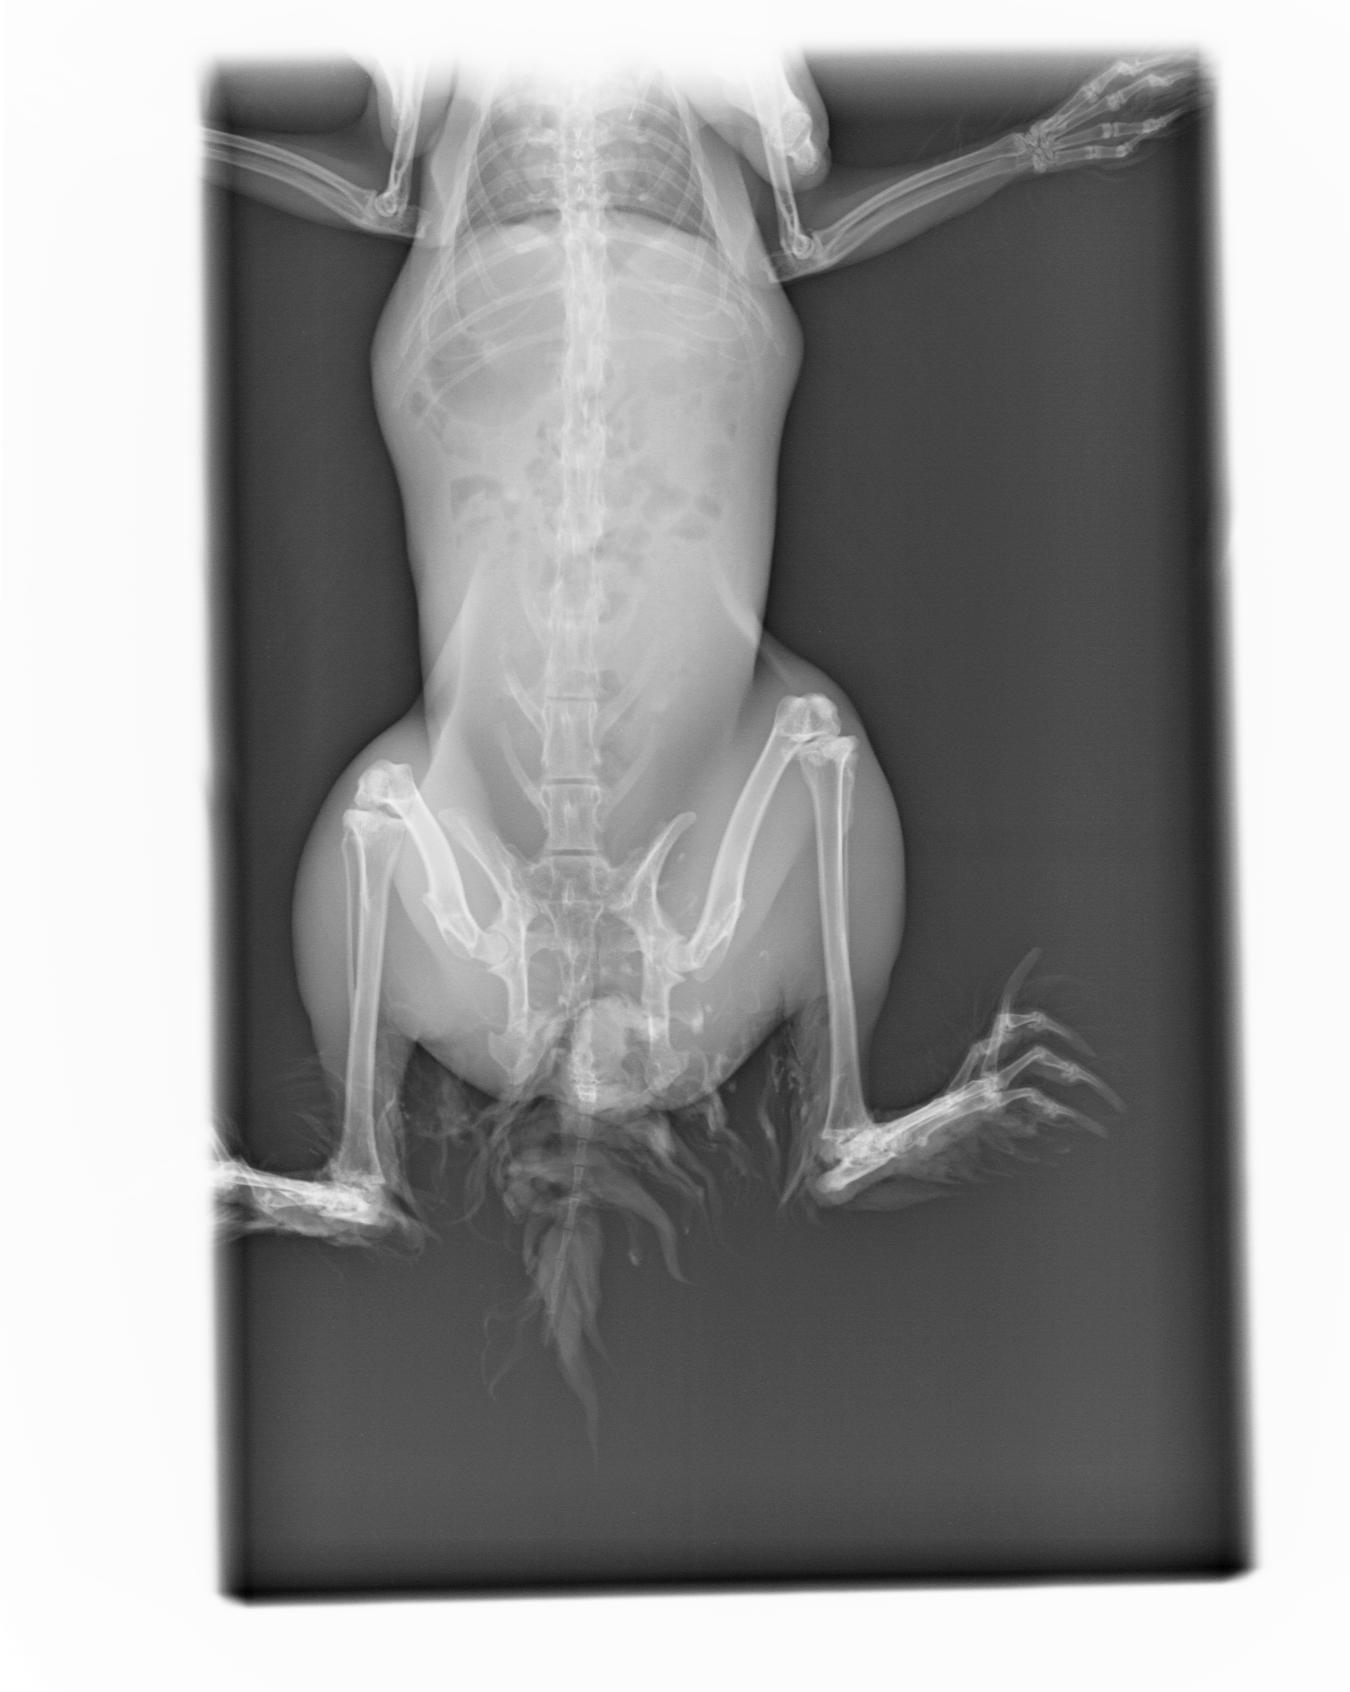

NAC lapins rongeurs

vos petits compagnons spécifiques seront reçus avec professionalisme

Radiologie Numérique

L'appareil de radiologie oriente le diagnostic en matière d'orthopédie ( os), en pneumologie et en médecine interne .

Le développement numérique assisté par ordinateur

facilite le diagnostic en retravaillant l 'image par informatique. Le client repart avec son cliché radio sur sa boite email.